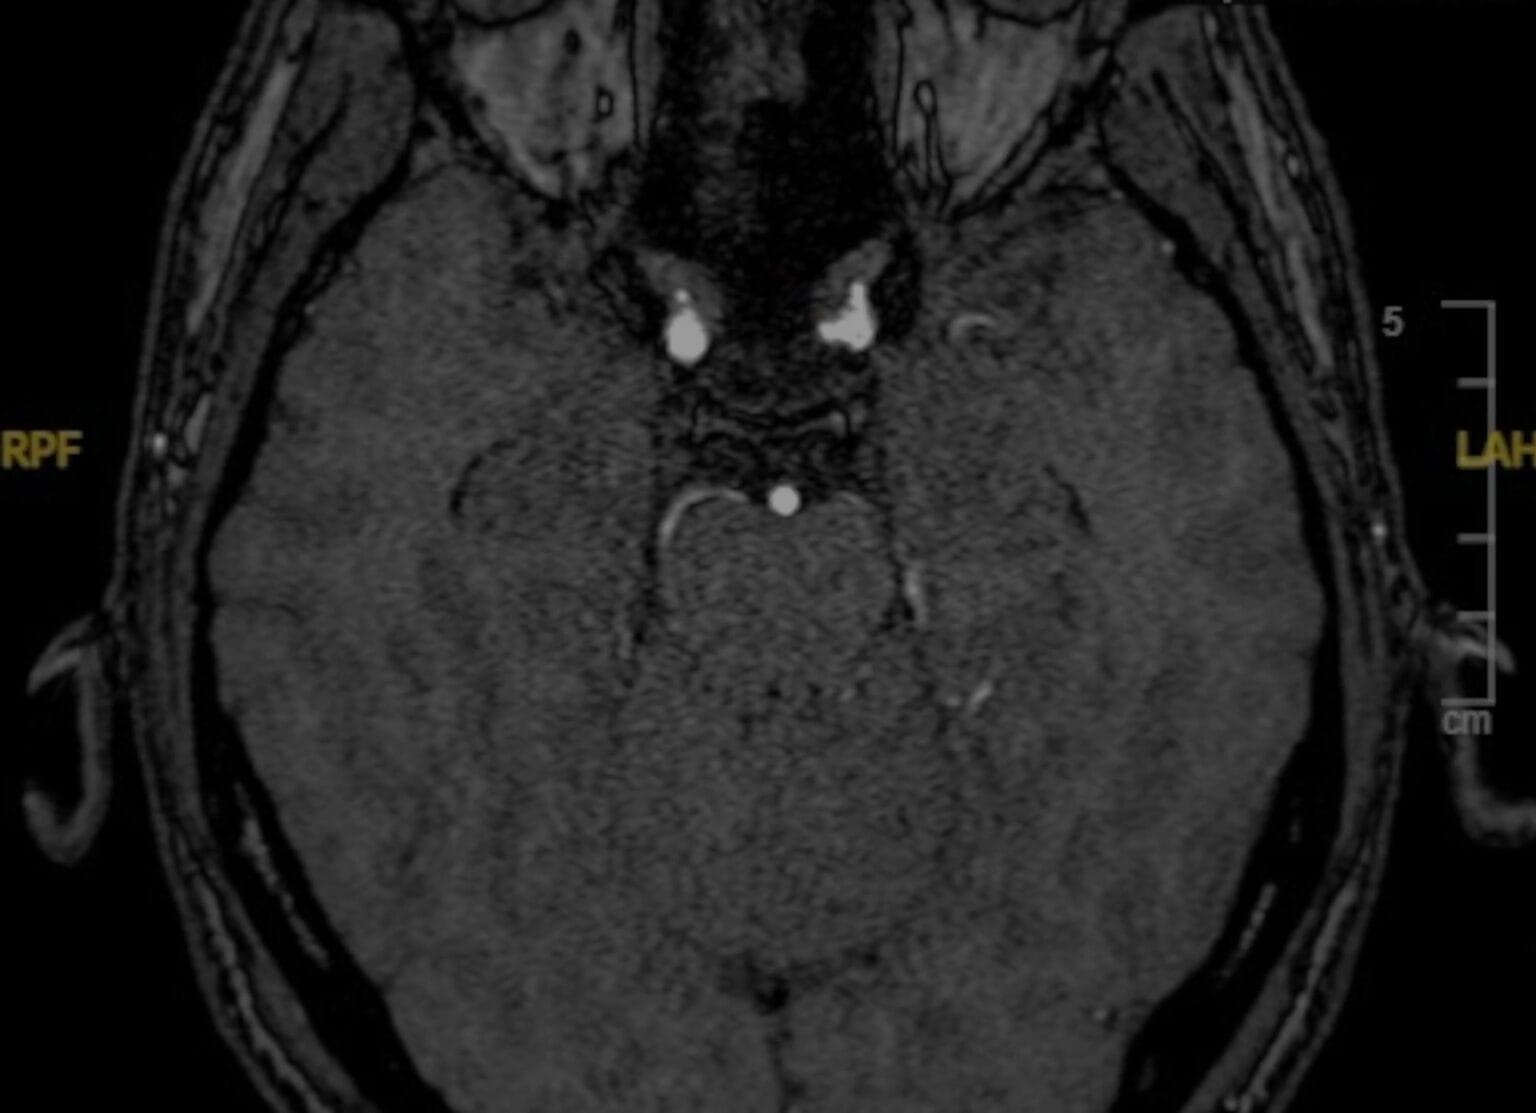

Aneurisma de la arteria hipofisaria superior – Clinoidectomía Intradural

El Dr. Javier Ibáñez realiza una clinoidectomía intradural y apertura de los anillos durales para abordar un aneurisma hipofisario superior.

Clipaje transcavernoso de aneurisma de la ACS

Se presenta un caso de clipaje de un aneurisma de la arteria cerebelosa superior con un tratamiento previo con flow-diverter fallido.